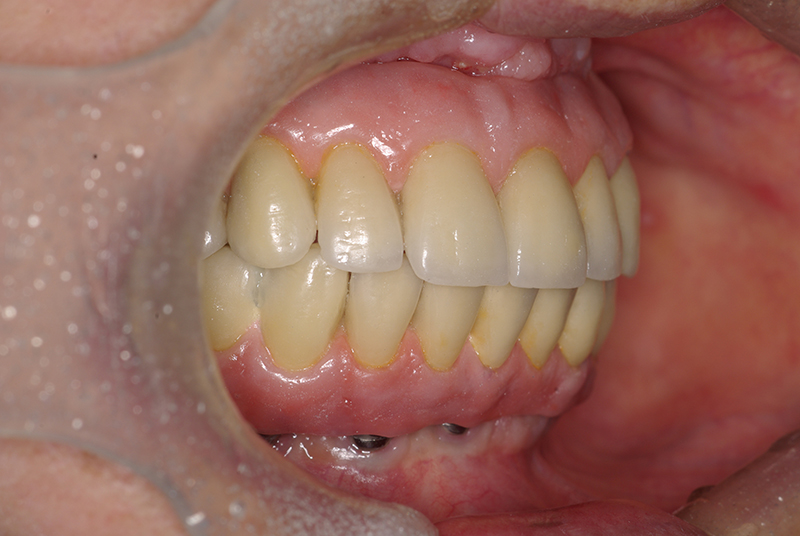

Na Clínica Pontes Odontologia, somos referência em implantes dentários em Fortaleza, oferecendo tratamentos de alta qualidade e tecnologia de ponta. Os implantes dentários são estruturas de titânio posicionadas cirurgicamente no osso maxilar ou mandibular para substituir as raízes dos dentes ausentes. Essa técnica permite a fixação de próteses personalizadas, restaurando a função mastigatória, a estética e a autoestima dos nossos pacientes.